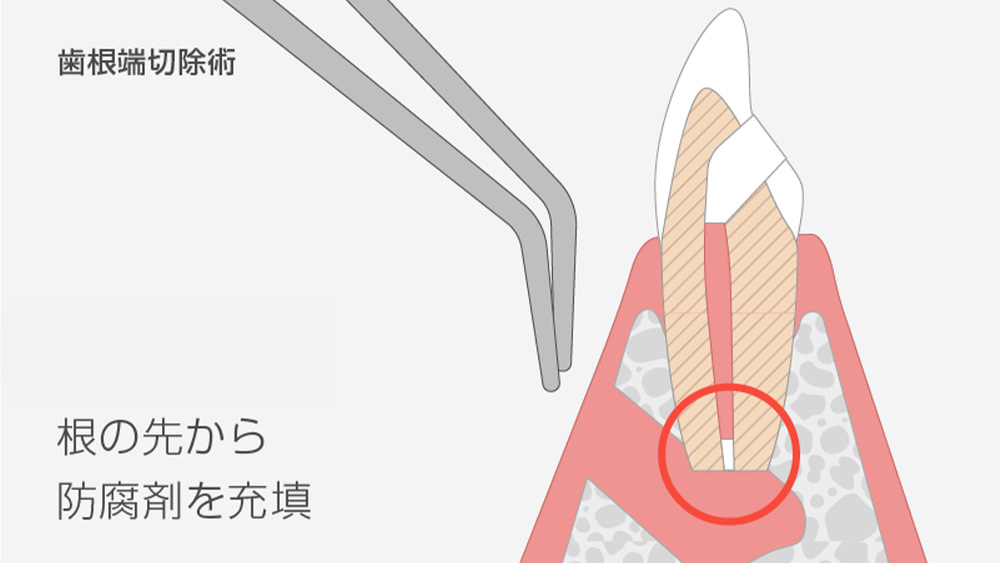

歯の根の先に問題がある場合の

選択肢

根管治療をしても、歯の根の先に膿が溜まるなどの問題が改善しない場合、歯根端切除術という外科的な処置を検討することもあります。

これは、歯ぐきを切開し、歯の根の先端部分と病巣を直接取り除く治療です。

一般的な根管治療では対応が難しいケースでも、この方法によって大切な歯を残せる可能性があります。